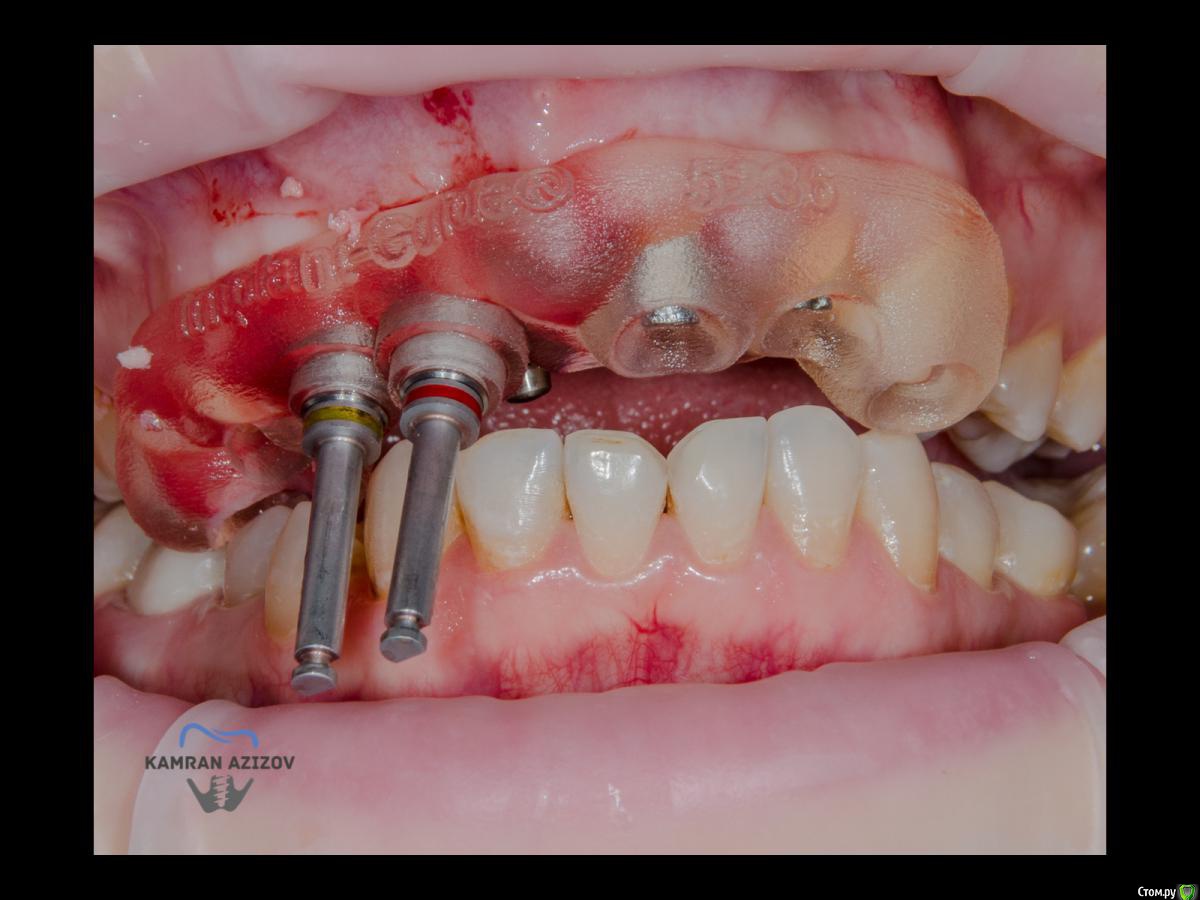

kamranchick Опубликовано 6 апреля, 2019 Поделиться Опубликовано 6 апреля, 2019 (изменено) Хай Гайсдавно ничего не комментировал и не выкладывал, что то настроения не было, да и муза не посещалаСитуация следующаяпришла пациентка, жалобы на неприятный запах из рта, сначала не понял что за хрень, ну как распилил мост понял че к чему... халтура.Ну и по кейсуУдаление клыка и 2ки, через 2 месяца навигация, имплантация + Шашлыки по карлоссу, смена формиков, временное протезирование. только мягкие ткани, Изменено 6 апреля, 2019 пользователем kamranchick 7 1 Ссылка на комментарий

pit Опубликовано 7 апреля, 2019 Поделиться Опубликовано 7 апреля, 2019 Четыре вопроса.Почему нельзя было прибегнуть к ортодонтии? Почему нельзя было просто удалить 13 зуб и сделать новый мост?Почему нельзя было удалить еще и 14 зуб, установить 2 винта в позиции 14 и 12 (или11) и сделать все за один хирургический этап, и сразуже нагрузить?Почему были использованы позиции имплантов 13 и 12, а не 13 и 11? 3 Ссылка на комментарий

kamranchick Опубликовано 8 апреля, 2019 Автор Поделиться Опубликовано 8 апреля, 2019 ТакУважаемый Петр) начнем по порядку1. пациентка отказалась от нее, как только не уговаривал ее, просто танцы с бубном были)2. после удаления клыка сразу ушел хиленький резец, делать мост 14-21-22 как то страшновато было из-за протяженности дефекта3. 1.4 зуб жалко было удалять, зачем удалять еще один зуб если так и так 2 имплантата, ну как вариант можно было бы, было бы легче позиционировать имлпнтататы4. в позиции 1.1 был большой резцовый канал, не захотелось проводить какие то манипуляции вокруг него и с ним, ну как то так)) Ссылка на комментарий

pit Опубликовано 9 апреля, 2019 Поделиться Опубликовано 9 апреля, 2019 ТакУважаемый Петр) начнем по порядку1. пациентка отказалась от нее, как только не уговаривал ее, просто танцы с бубном были)2. после удаления клыка сразу ушел хиленький резец, делать мост 14-21-22 как то страшновато было из-за протяженности дефекта3. 1.4 зуб жалко было удалять, зачем удалять еще один зуб если так и так 2 имплантата, ну как вариант можно было бы, было бы легче позиционировать имлпнтататы4. в позиции 1.1 был большой резцовый канал, не захотелось проводить какие то манипуляции вокруг него и с ним, ну как то так))Поняно По пункту 4, если формировались лоскуты, почему бы не убрать содержимое резцового канала и не использовать позицию 11з? Ведь, с точки зрения эстетики, позиция 11 з выгоднее. Между двумя рядом стоящими имплантами сосочка никогда не будет. Ссылка на комментарий

Дмитрий М Опубликовано 9 апреля, 2019 Поделиться Опубликовано 9 апреля, 2019 kamranchick11з консоль, или это единая конструкция? Ссылка на комментарий

kamranchick Опубликовано 9 апреля, 2019 Автор Поделиться Опубликовано 9 апреля, 2019 kamranchick11з консоль, или это единая конструкция?13-12 с консолью на 11 Ссылка на комментарий

kamranchick Опубликовано 9 апреля, 2019 Автор Поделиться Опубликовано 9 апреля, 2019 Поняно По пункту 4, если формировались лоскуты, почему бы не убрать содержимое резцового канала и не использовать позицию 11з? Ведь, с точки зрения эстетики, позиция 11 з выгоднее. Между двумя рядом стоящими имплантами сосочка никогда не будет.Да можно было быНаверное из за нехватки опыта работы с резцовым каналомОдин раз делал Ну и мнения расходятсяКто то говорит что пациенты теряют частично чувствительность, кто то говорит что все нормально... взвесив все на чаше весов, решили канал не трогать Ссылка на комментарий